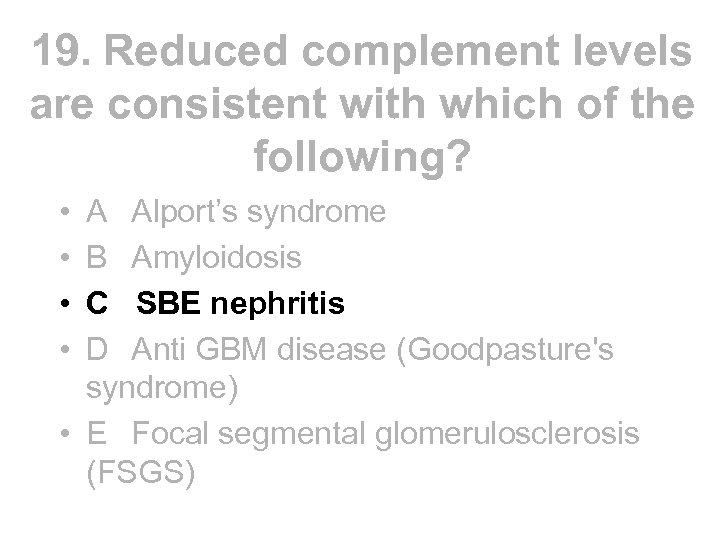

Reduced serum complement • • Occurs in: - SLE - infective endocarditis - post strep nephritis - shunt nephritis - cholesterol embolism - cryoglobulinaemia - MCGN types 1 and 2 • • Complement normal in FSGS, amyloidosis, Alports, anti GBM disease C 3 nephritic factor is an Ig. G auto antibody to the C 3 convertase of the alternative pathway of complement activation, found in both types of MCGN